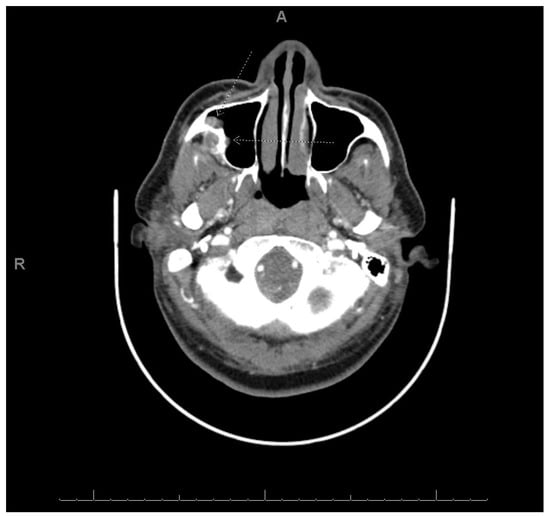

2.1. Case 1

2.2. Case 2

2.3. Case 3

| Age/Sex | 54-year-old female | 49-year-old female | 40-year-old male |

| Presentation | Painful mass | Painful mass | Mass recurrence |

| Location | Right maxilla | Right mandible | Right maxilla |

| Staining/IHC | PAS (+) D-labile Mucicarmine (−), p63 (+) CK5/6 (+), CK19 (+) | PAS (+) D-labile Mucicarmine (−) CK5/6 (+) | H&E only |

| Morphology | Infiltrative, non-encapsulated malignant neoplastic odontogenic epithelial proliferation with clear cell component in a dense fibrous connective tissue stroma. Neoplastic cells arranged in anastomosing trabeculae. Nuclear hyperchromasia and pleomorphism surrounded by clear, vacuolated cytoplasm. Stroma was hyalinized, densely collagenized, hypocellular, and hypovascular. | Neoplastic odontogenic epithelial proliferation diffusely infiltrated the connective tissue stroma. Neoplastic cells arranged in islands of variable size, trabeculae, and nests. Nuclei were hyperchromatic, central, and pleomorphic surrounded by clear cytoplasm. | Infiltrative odontogenic epithelial neoplasm intermixed with eosinophilic dentinoid matrix. Neoplastic cells arranged in infiltrative, non-encapsulated sheets, cords, and nests of polygonal cells with central hyperchromatic and slightly pleomorphic nuclei surrounded by clear cytoplasm and occasional pale eosinophilic cytoplasm. Occasional mitotic figures were noted. Neoplastic epithelial sheets and cords blended with eosinophilic cellular matrix without cellular rimming consistent with dentinoid deposits. |

| Procedure | Right maxillectomy with negative margins | Left mandibulectomy Right temporomandibular joint arthroplasty Left fibula free flap | Right maxillectomy without orbital exenteration Right selective neck dissection Forearm free flap Four months adjuvant radiation |